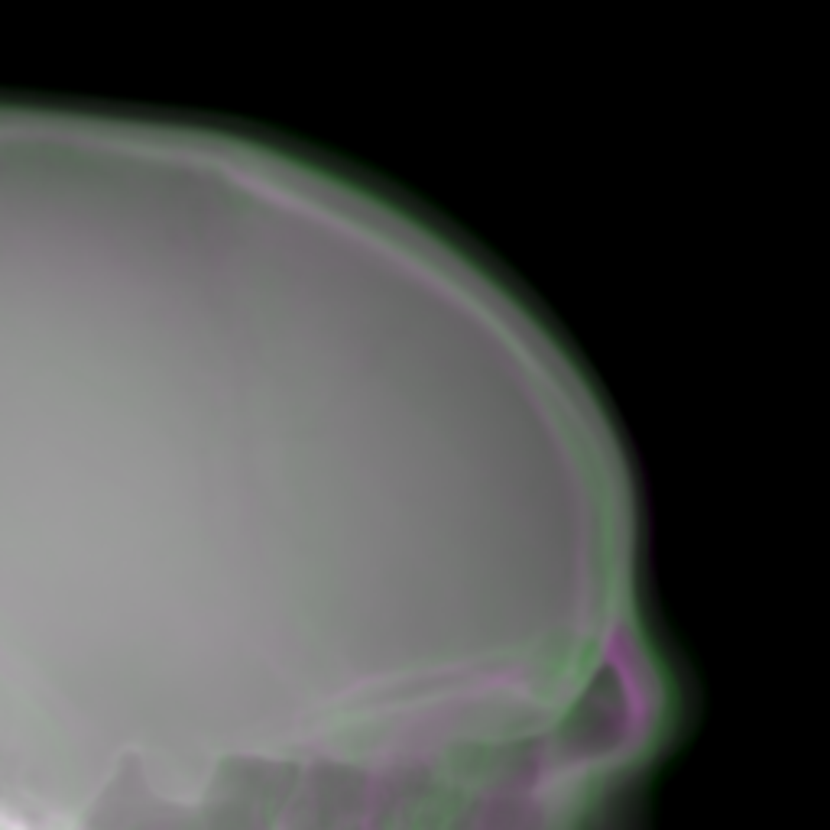

To combine such dual projection information, we convert the patches from 0superscript00^{\circ} and 180superscript180180^{\circ} cone-beam projections to 3-channel patches forming RGB color patches. The 0superscript00^{\circ} patch is used for the red and blue channels, while the 180superscript180180^{\circ} patch is used for the green channel. The 0superscript00^{\circ} patch instead of the 180superscript180180^{\circ} patch takes two channels, since the target cephalograms are also acquired in the 0superscript00^{\circ} view in our setting. In the RGB patch, the intensity difference between the 0superscript00^{\circ} patch and the 180superscript180180^{\circ} patch is revealed by the color: grey areas have the same values for the three channels, indicating that the intensity values from the 0superscript00^{\circ} and 180superscript180180^{\circ} patches respectively are close to each other, while green areas indicate that the 180superscript180180^{\circ} patch has larger values and magenta areas indicate that the 0superscript00^{\circ} patch has larger values. An example is displayed in Fig. 5, where Figs. 5(a) and (b) are the 0superscript00^{\circ} and 180superscript180180^{\circ} patches respectively, Fig. 5(c) is the RGB patch as the input of the neural network, and Fig. 5(d) is the corresponding target output of the neural network.

The cephalogram synthesis results of two patches and one complete stitched cephalogram are displayed in Fig. 10. In the top row, the blue curve is the outline of the target patch, while the red and green curves are the outlines for the 0superscript00^{\circ} and 180superscript180180^{\circ} projections, respectively. Consistent with the relationship in Fig. 4, the blue curve is between the red and green curves. Since the 180superscript180180^{\circ} projection (green channel) has larger area than the 0superscript00^{\circ} projection (red and blue channels), the region near the boundary appears green in the RGB input patch in Fig. 10(c). Fig. 10(d) is the target output. Fig. 10(e) is the output using the 0superscript00^{\circ} projection only, where the outline has large deviation from the target blue curve. In contrast, in Fig. 10(f) where the dual projections are used, the outline is closer to the target blue curve. In the middle row, the sella turcica in the 1-projection output has large distortion, as indicated by the arrow in Fig. 10(k), compared with that in the target patch. On the contrary, the sella turcica in the 2-projection output (Fig. 10(l)) preserves its shape. These observations highly demonstrate the benefit of using dual projections.